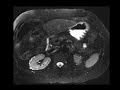

Lithium Nephropathy

MRI images demonstrate innumerable tiny T2 hyperintese, T1 hypointense foci at the margins of both kidneys in a patient with known lithium nephropathy.